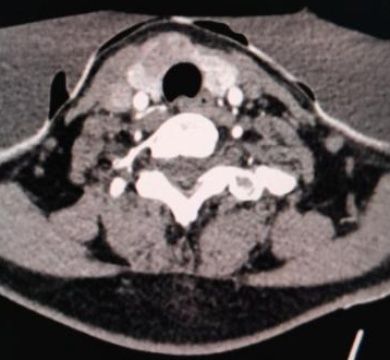

(a) (b) (c) (d)

(a)~(d)甲状腺滤泡性腺瘤患者双能量CT增强扫描动脉期原始图像、碘图、Rho/Z图及病理图

Figure 1. Examples of dual-energy CT arterial phase images, iodine uptake images, Rho/Z images, and pathological findings in three groups of patients with thyroid nodules (HE, ×100, H) (Rho/Z, Electron Density/Effective Atomic Number)

1. 三组甲状腺结节患者双能量CT动脉期图、碘图、Rho/Z图及病理图示例(HE, ×100, H) (Rho/Z,电子密度云/有效原子序数)